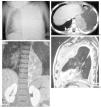

Se trata de un niño de 3 años de edad que comienza con neumotórax derecho a tensión (fig. 2A). Tras el drenaje del mismo se observa la existencia de una lesión quística en la base pulmonar derecha. En la TC de tórax se confirma la lesión quística en el lóbulo medio que se interpreta como una MAQ (fig. 2B). Se realiza lobectomía con diagnóstico histológico de BPP tipo I. A los 4 meses presenta una metástasis pleuropulmonar en el hemitórax derecho, que se resuelve tras quimioterapia y cirugía. Un año después presenta una nueva recidiva, con metástasis subpleural basal derecha (fig. 2C); se le realiza una tercera toracotomía para la escisión lesional, confirmándose de nuevo su naturaleza metastásica. Después de 6 años de evolución el paciente se encuentra estable y libre de enfermedad.

Fig. 2. Caso 2. (A) Radiografía anteroposterior de tórax. Neumotórax derecho a tensión con desplazamiento contralateral de estructuras mediastínicas. (B) Tomografía computarizada de tórax, corte axial. Masa pulmonar quística localizada en el lóbulo medio que correspondió a un blastoma pleuropulmonar tipo I. (C) Resonancia magnética abdominal en secuencia potenciada en T1 con gadolinio, corte axial al nivel hepático. Lesión metastásica subpleural hipercaptante.